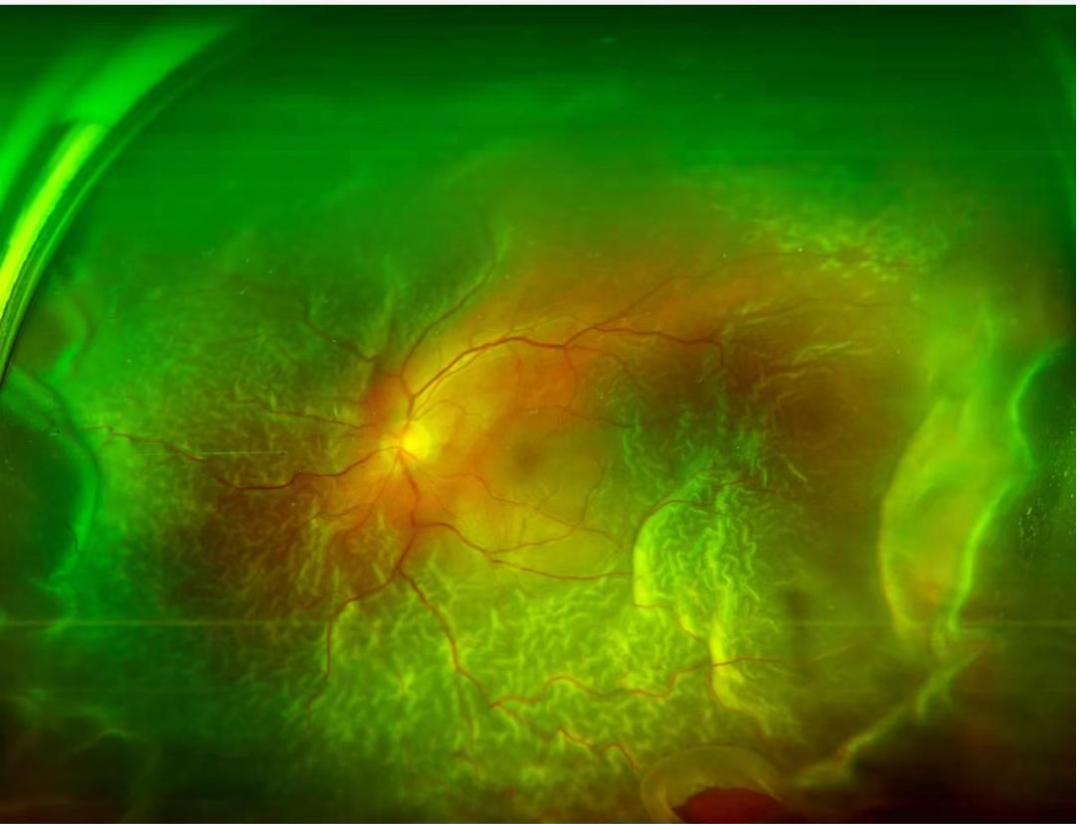

部分眼底病病病变图片

视网膜脱离

视网膜分支静脉阻塞

星状玻璃体变性

糖尿病视网膜眼底改变